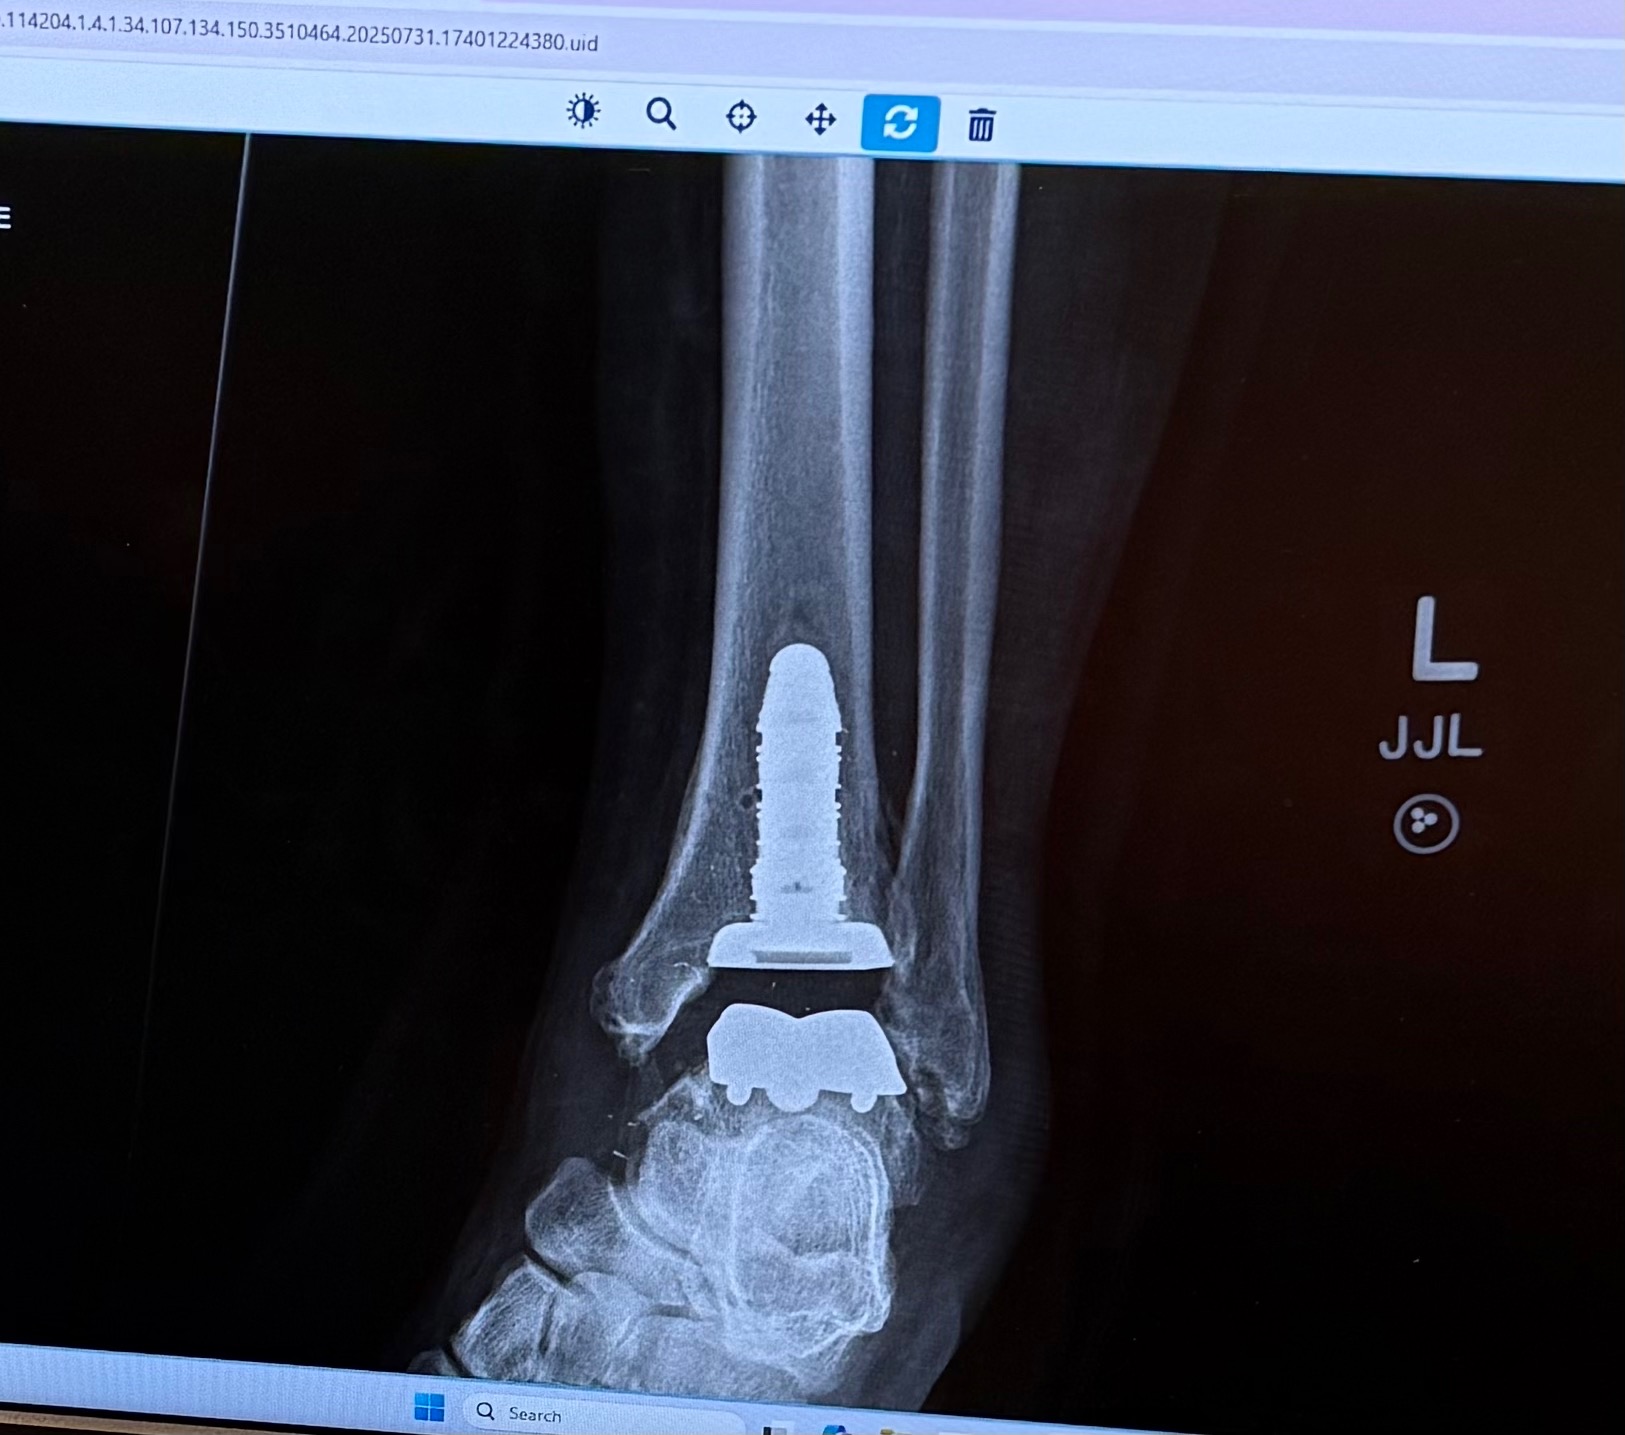

Hi! Our names are Doug Bridge and Jim Hill and we've set up this GoFundMe for a good friend of ours, Russell "Rusty" Roseman. Most likely you know him from seeing him at Fry's, where he has worked for the past 23 years. He's been there when you were looking for something that you just couldn't find on your own. Or you might know him as the first smiling face you used to see greeting you on Sunday mornings at his church. Or perhaps you know him from his new area of service in the Special Needs program there. Either way, if you've met Rusty you know that he loves people and shows it with his ever present smile. What you might not know is that recently he has been sidelined with a very painful ankle issue that has actually required total ankle replacement surgery. He has been off work since May 20th and at this time we're not sure when he will be able to return. Things have been tough and financially things have gotten really tight. Between monthly expenses and medical and physical therapy costs he is barely hanging on. And the bills that haven't yet arrived could be staggering. This is why this account has been set up. Rusty is going to need help from all of us! Thank you in advance for helping Rusty! And thank you, too, for your prayers regarding his physical recuperation.